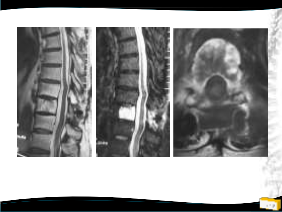

OLGU

• 55y, E

• Akciğer Ca

• T10 metastaz

• Sırt ağrısı

• Min. paraparezi

2 yıl takip ediIdi, sorun olmadı